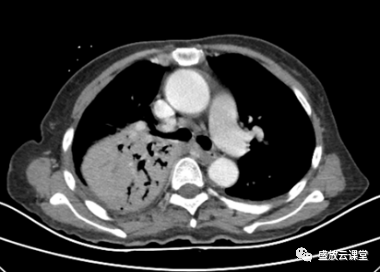

【病例】肺淋巴瘤(MALT)一例CT影像

【病例】肺淋巴瘤(MALT)一例CT影像-5 【病例】肺淋巴瘤(MALT)一例CT影像-6

【病例】肺淋巴瘤(MALT)一例CT影像-4